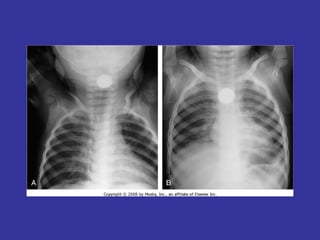

PNEUMONIA  Inflammation and infection of the lung parenchyma due to bacterial or viral  pathogens. Classified by anatomy:  Lobar, Interstitial, Bronchopneumonia Etiology: Viral:   Adenovirus, Influenza, RSV Bacterial:   Neonates:  GBS, Chlamydia, E. coli, Listeria monocytogenes  1month-6 years:  S. pneumonia, H. influenza Adolescents:  S. pneumonia, Mycoplasma pneumonia Immunocompromised:  Pseudomonas, klebsiela, Fungi, PCP

Epidemiology:   Children 2-4 years, are more susceptible than older children May follow epidemics of viral infection Winter/spring most common Day care/ kindergarten S/S:   Tachypnea,  dyspnea,  cough,  intercostal retractions, nasal flaring,  grunting,  fever,  accessory resp. muscles usage,  chest pain,  lethargy,  hypoxia, rales/crackles,  decreased  breath  sound/dullness to percussion (consolidation). LAB:   CBC:   WBC with left shift,  Blood culture (if severe picture),  Pleural fluid studies (effusion),  ABG  CXR:   Lobar consolidation ( S. pneumonia and H. influenza ),  Hilar adenopathy ( TB ),  Pneumatoceles ( S. aureus/G- ),  Bilateral diffuse infiltrate ( Mycoplasma ),  Abscess ( klebsiella ) Mycoplasma:  Presence of Cold agglutinin titers Prevention:   Pneumovax vaccine in immunocompromised children, SC Ds.